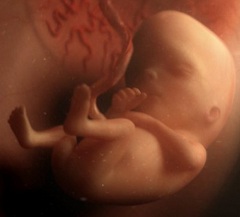

Размер плода на 13 неделе беременности достигает 7 см, а весит он около 23 г. Тело его постепенно вытягивается в длину, и соотношение голова/туловище постепенно уменьшается, поэтому голова выглядит уже не такой большой.

Движения плода на 13 неделе беременности активные и не такие хаотичные, как прежде. Это можно заметить на УЗИ в 13 недель беременности. Малыш ощупывает части своего тела, пуповину, строит гримасы и потягивается. Он еще не видит – глазки прикрыты веками, но уже реагирует на свет. Мимическая мускулатура пока сформирована таким образом, что малыш только хмурится и «сердится». Мышцы, формирующие непроизвольную улыбку, еще недоразвиты.

В коже плода образовались тактильные рецепторы, благодаря чему он ощущает прикосновения и давление. Будущий ребенок с 13 недель беременности реагирует на смену положения матери, и сам по несколько раз в день меняет свою позу в матке. Сформировались потовые железы в коже, а на голове – первые волосы.

На этом сроке сердце плода уже заключено внутри грудной клетки, спереди защищено хрящевой основой грудины, появились зачатки ребер. В скором времени малыш будет пытаться совершать тренировочные дыхательные движения.